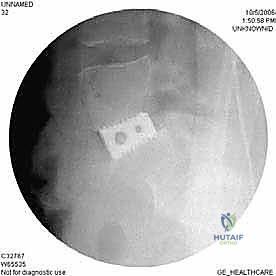

الخطوة 4: التحضير وزراعة القفص (Implant Insertion)

يتم قياس الفراغ المتبقي بدقة لاختيار الحجم المثالي للقفص الجراحي (Cage). يُصنع هذا القفص عادة من مادة PEEK أو التيتانيوم، ويتم حشوه بمادة عظمية (طعم عظمي ذاتي من المريض، أو طعم صناعي، أو بروتينات محفزة لنمو العظم BMP). يتم إدخال القفص بقوة في الفراغ، مما يؤدي فوراً إلى استعادة ارتفاع القرص الطبيعي وتوسيع المخارج العصبية (تخفيف الضغط غير المباشر).

الخطوة 5: التثبيت (Fixation)

لضمان أقصى درجات الثبات والسماح للعظم بالاندماج بمرور الوقت، يتم تثبيت القفص باستخدام شريحة معدنية صغيرة ومسامير من التيتانيوم تُثبت في الأجسام الفقرية من الأمام. في بعض الحالات، قد يرى الدكتور هطيف ضرورة إضافة تثبيت خلفي بمسامير عبر الجلد (Percutaneous Pedicle Screws) لزيادة الدعم.

الخطوة 4: التثبيت القوي (Rigid Fixation)

نظراً لضخامة الفراغ الذي تم تعويضه، يتطلب الأمر تثبيتاً قوياً جداً. يتم استخدام شرائح تيتانيوم طويلة ومسامير من الأمام، وفي الغالبية العظمى من الحالات، يتطلب الأمر إجراء مرحلة ثانية لتثبيت العمود الفقري من الخلف بمسامير وقضبان لضمان استقرار البناء الجراحي بزاوية 360 درجة.